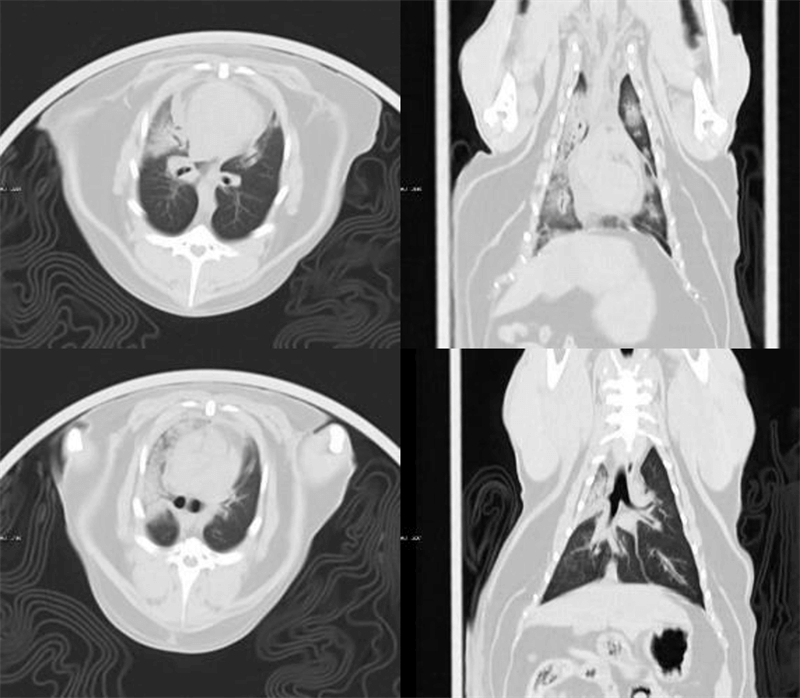

臨床畫廊